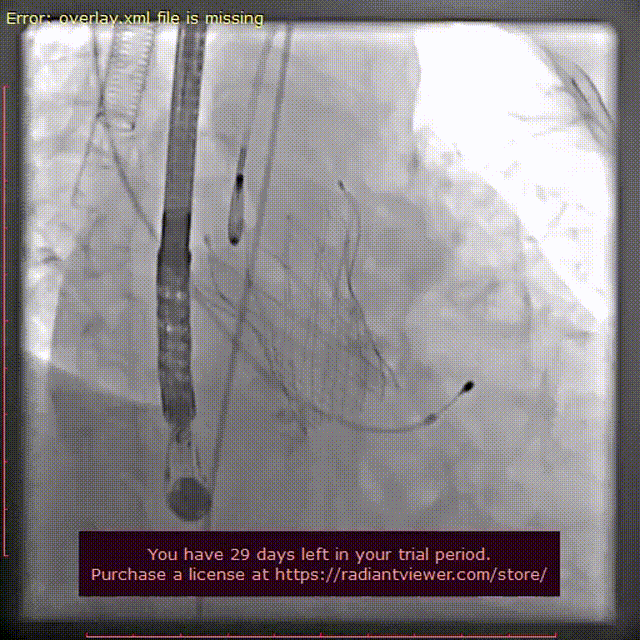

完全释放后位置良好,由于受重度钙化影响,瓣膜受到一定压缩,有轻-中瓣周漏,于是180次起搏下使用22mm球囊后扩,后扩完瓣膜形态良好。

术后主动脉根部造影

后扩后主动脉根部造影